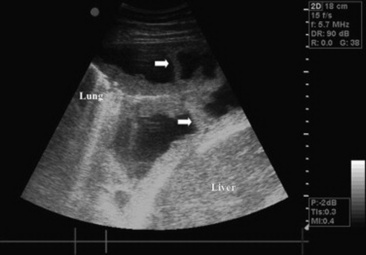

Ultrasonography

Thoracic ultrasonography, a companion to thoracic radiography, is useful for diagnostic, therapeutic, and prognostic evaluation of the extraparenchymal thorax, the pleural space, and the peripheral (superficial) parenchyma of the lung. Unlike thoracic radiography, in which specialized equipment is needed to image the adult large animal, thoracic ultrasonography is an imaging technique readily available to most practitioners. In many instances it is superior to thoracic radiography as an imaging method; examples include evaluation of pleural effusions, assessment of thoracic trauma, evaluation of neoplasms or granulomata, detection of mediastinal masses or abscesses, and guidance of transthoracic lung biopsy.9,10 Ultrasonography is considered greatly superior to thoracic radiography in the detection of rib fractures.11 This imaging technique should be considered for complete evaluation of any large animal with suspected or diagnosed pulmonary disease.

Although ultrasound waves will not penetrate the aerated portion of the lung, limiting the examination to extraparenchymal surfaces in normal horses, ultrasonography is superior to thoracic radiography in evaluation of these areas of the chest. Small amounts of pleural fluid that would be missed on auscultation, percussion, or thoracic radiographs can be detected, and the amount and character of pleural effusion in each hemithorax can be separately evaluated.9 Clear fluid is anechoic, but inflammatory cells, gas, and fibrin are echogenic, causing opacities that can be seen floating in pleural fluid and altering the general echogenicity of the fluid. Because of this, ultrasound is the method of choice for diagnosis and monitoring of pleural space disease. Ultrasonography should be used to guide catheter placement for drainage of accumulated fluid in the pleural space. The pleural surfaces are imaged well by ultrasound, with thickened or roughened areas easily detected. Lack of normal independent movement of the visceral and parietal pleural surfaces during the respiratory cycle, suggestive of adhesion formation, can be readily monitored.9,10

Consolidated lung is a better acoustic medium than aerated parenchyma and can be well visualized. If there is pleuropneumonia with consolidation or atelectasis caused by compression of the ventral lung by pleural effusion, it will be evident. Pulmonary abscesses or masses extending to the lung surface can be imaged, and ultrasound can be used for guidance for transthoracic biopsy.9,10 Thoracic radiography remains superior to ultrasound in diagnosis of pulmonary parenchymal disease and pneumothorax, but combined the two techniques will improve patient management diagnostically and therapeutically.

image

Fig. 31-3 Thoracocentesis and therapeutic drainage in the horse. Pleural effusion can be large and bilateral. Samples should be obtained for culture and cytologic examination at the time the chest is drained.

Courtesy Dr. Corinne Sweeney, University of Pennsylvania, New Bolton Center, Kennett Square, Penn.